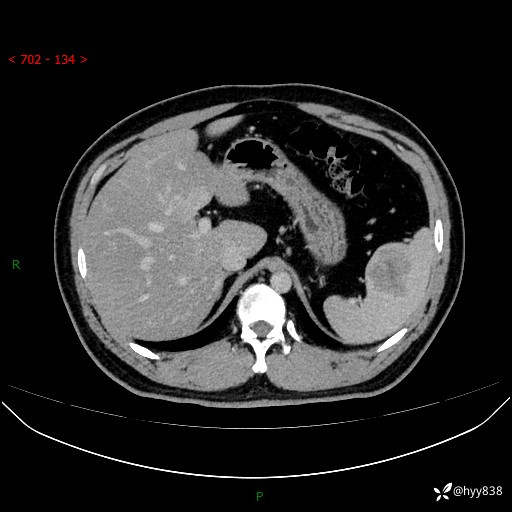

【患者信息】:31岁/男

【主诉】:超声发现脾脏肿物,为进一步诊治来我院,门诊以“脾脏占位”收入院

【检查】:上腹部CT平扫+增强